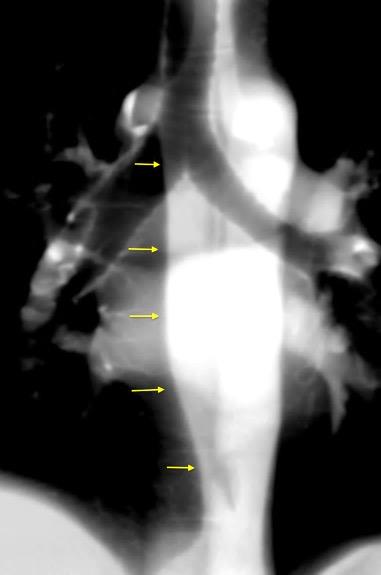

Líneas paraespinales formando un “paréntesis” por encima del diafragma. El signo señala el origen “intratorácico” de la lesión.

Conrad A et al. Pott’s disease associated with large and multiple abscesses in a 30-year-old migrant from Chad. BMJ Case Rep 2018

(lesiones toracoabdominales) La divergencia de las líneas paraespinales apunta a lesión toracoabdominal, que desde el tórax desciende y penetra en el abdomen.

Signo del “iceberg” positivo en Tb vertebral

Afectación por vía hematógena. Región dorsolumbar más frecuente. Afectación inicial: irregularidad de los platillos vertebrales, disminución del disco intervertebral con esclerosis ósea adyacente. Kim. Radiographics.2001